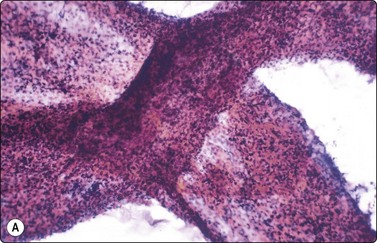

Tumors of more than one histologic type (mixed forms) (Figs 13.35 and 13.36)14,60,63,65

While the basic GCT types are infrequent in pure forms they are very frequent in mixed forms. Embryonal carcinoma and teratoma are each present in 47% of cases, and yolk sac tumors in 41%; 40% of TGCT contain varying numbers of syncytiotrophoblastic cells.12

image

Fig. 13.35 Tumor of more than one histological type (mixed form)

Large bisected tumor occupying most of the enlarged testicle in a male 19 years of age. Note hyalinized, degenerate and cystic areas.

image image

Fig. 13.36 Tumor of more than one histological type (mixed form)

(A) Well-differentiated glandular epithelium (right), large malignant cells similar to embryonal carcinoma (left) (MGG, HP); (B) Corresponding tissue section (A, H&E, IP; B, PAP, IP).

Criteria for diagnosis

Cellular aspirates; necrosis and hemorrhage frequent,

Three-dimensional clusters of epithelial malignant cells as described above

Coexisting teratomatous structures represented by mature or immature tissues originating from one or more blastodermal leaf: fusiform naked nuclei embedded in a myxoid background resembling embryonal mesenchyme; islets of cartilage; sheets of epithelial cells, which may be squamous, ciliated or intestinal (with goblet cells); bundles of fusiform cells with blunt ends reminiscent of leiomyoma; tight clusters of deeply stained bare nuclei may correspond to primitive neuroectodermal tissue.

The diagnosis of mixed forms is simple when malignant elements of an epithelial nature coexist with clear-cut teratomatous structures. Necrosis may obscure the neoplastic cells and the teratomatous component may be only minor or even absent. This can be explained by its greater cohesion causing under-representation in FNA samples. As a result, the differential diagnosis between mixed TGCT and embryonal carcinoma is sometimes difficult or impossible.14,59-61,65,66 The presence of multinucleated syncytial cells is not diagnostic of choriocarcinoma.